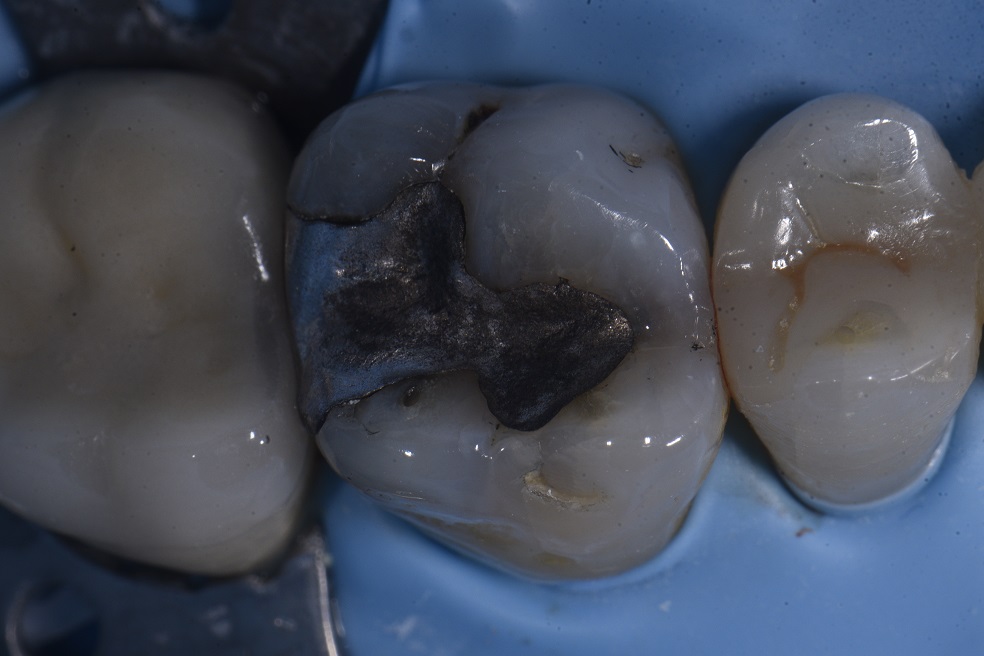

Supercomposite replacement of an amalgam – fitting as Grandio SO is actually referred to as white amalgam. Yes, we are watching the P pit and have always been watching it – the Diagnodent does not light up at all when over it.